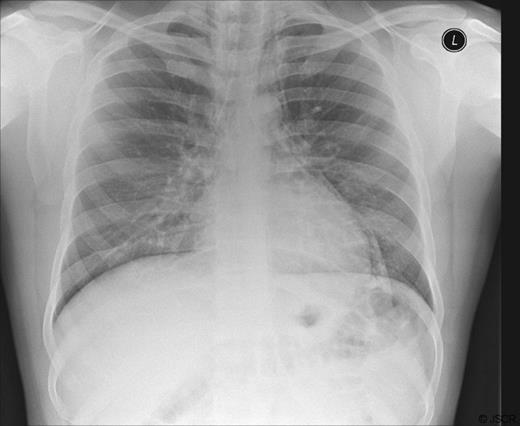

Reassessment of the patient's personal history revealed that he had nasally inhaled powdered cocaine prior to the onset of his symptoms. He denied the use of other recreational substances although he admitted to a significant history of smoking and alcohol use. The patient was managed conservatively during the course of his admission with simple analgesia and IV maintenance fluids. Repeat chest radiographs demonstrated resolution of his pneumomediastinum. His condition rapidly improved and he was discharged with plans for outpatient review.